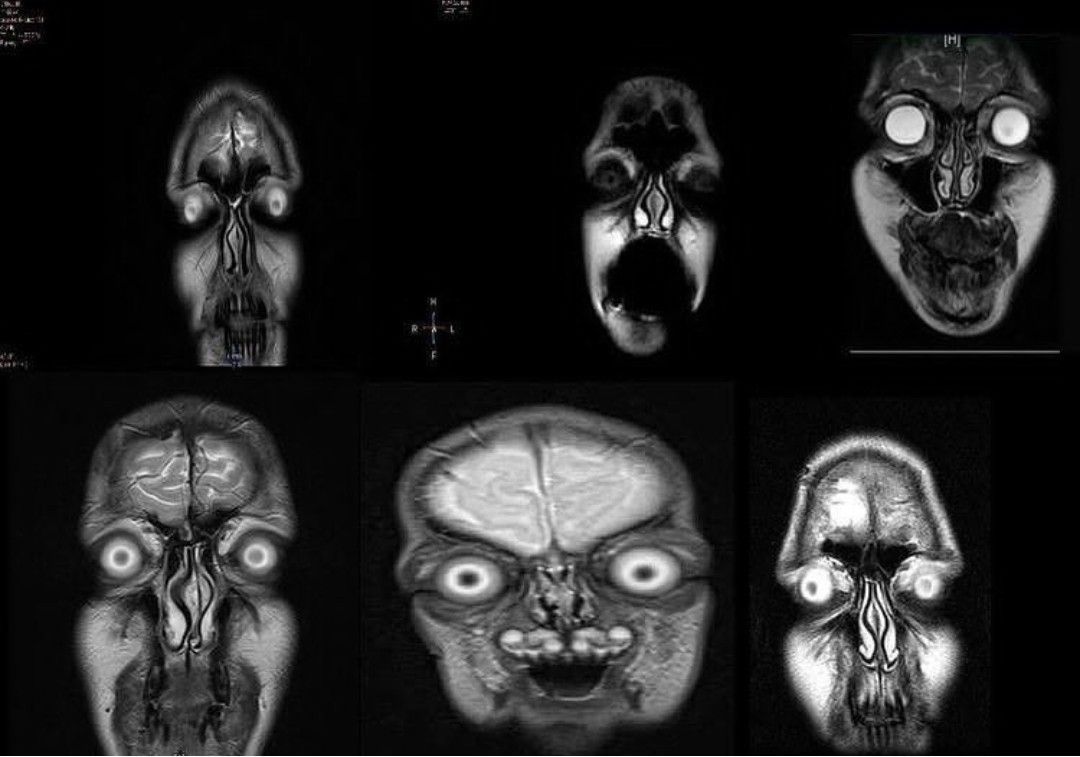

Never know front facing MRI are that scary 💀 A head MRI is a noninvasive imaging test that creates detailed pictures of your brain and surrounding tissues. An MRI allows your doctor to see inside your brain to check for diseases or injuries without having to do surgery. Your doctor can use the images to make a diagnosis and recommend the best treatment for your condition. An MRI uses powerful magnets, radio waves and a computer to take images of your brain. MRI images are clearer and more precise than other forms of diagnostic imaging. Unlike CT scans and x-rays, an MRI does not use radiation.